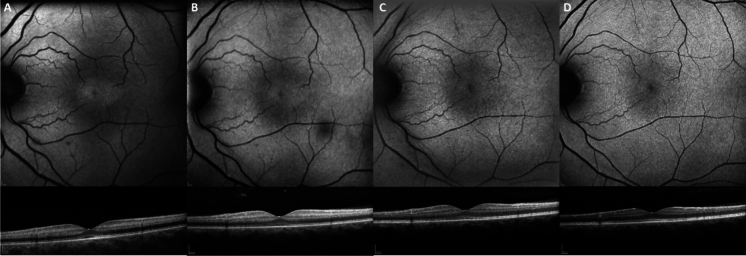

Methods: Serial assessments including: Medical history, visual acuity (VA), fundus autofluorescence, spectral-domain macular optical coherence tomography (OCT) and full-field electroretinogram (ffERG) were performed on 2 patients, between 2 and 47 days after quinine overdose.

Results: Both patients experienced a similar clinical course. After almost total vision loss within the first 24 h, VA dramatically improved by day 3. Early OCT changes demonstrated central macula hyperautofluorescence, which coincided with a hyperreflectivity of the macular inner retina on OCT. The initial ffERG findings demonstrated changes consistent with marked inner retinal dysfunction of the cone system, affecting both the cone ON- and OFF-bipolar cell pathways. In contrast, rod bipolar cell function was unaffected in the early phase of toxicity. Between days 10 and 17, the retinal arterioles showed narrowing which coincided with attenuation of ffERG parameters of rod system inner retinal function between days 10-40.

Conclusions: These cases suggest the early stages of quinine toxicity affect function of the presynaptic cone bipolar cell junction. This is then followed by retinal arteriolar attenuation and the well described electronegative scotopic ffERG.